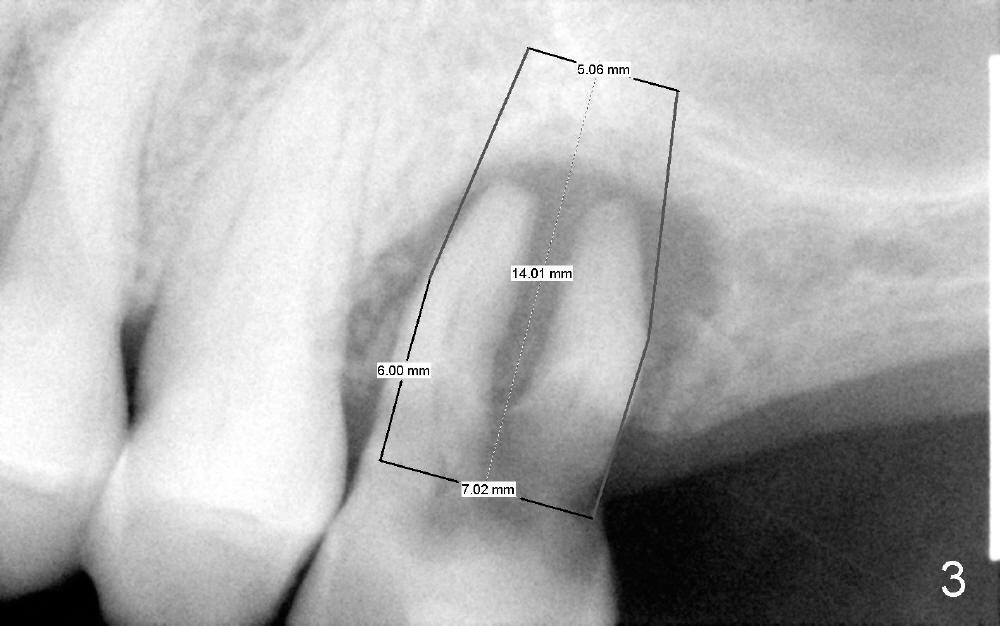

Since the socket is large, a large implant is planned to be placed (Fig.3, 7x14 mm) with sinus lift (penetrating the sinus floor for primary stability).